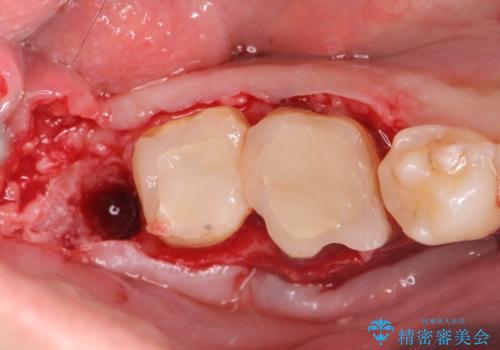

金属のクラウンは薄く加工しても壊れないことがメリットですが、セラミッククラウンを装着するにはスペースが少なすぎ、このまま治療を進めると外れやすく壊れ易いセラミッククラウンの設計となるため、歯周外科を行い狭小なスペースの拡大を行うこととしました。

なんとかギリギリのスペースを確保するこおtができ、無事銀歯を外してセラミック治療を行うことができました。